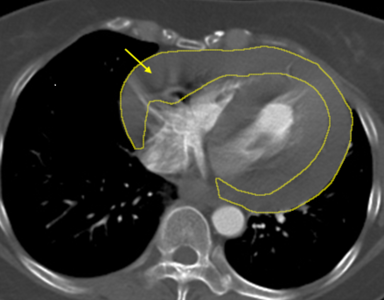

46歲的陳小姐長期反覆頭暈,但不以為意,日前騎機車返家突意識不穩而摔倒,緊急送醫院時已經休克,醫療團隊檢查發現她心臟外層迅速累積大量心包積血,高度懷疑合併外傷引發的「升主動脈剝離」,是死亡率極高的致命急症。在關鍵72小時內3次手術後,團隊將她從生死關頭拉回。 《詳全文...》